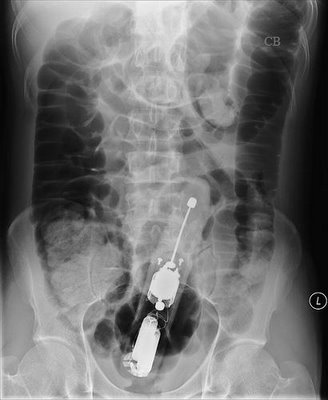

is that a TV remote? Or one of those cappuccino milk whisk things? 🙂

Is it concerning that the pt in the first X-ray has had their hip replaced?

To be fair - the person with the bottle up them appears to only have had half their hip done. Just the ball, not the socket.

They're female btw.

It's the unfixed fracture on the left rather than the hemiarthroplasty on the right I'd be more worried about.

(An A&E doc if that's any help - e-mail in profile)

dr_death - is it fractured or just the way the person is lying? Does the leg not tend to rotate outwards when the NOF is broken?

Looks more like OA than a fracture to me. But you're the expert.

the inserted object is quite clearly photoshopped (it's a plastic bottle, plastic is radiolucent....)

Has to be said the x-ray is too bollocks to be certain but the neck on the left certainly looks shorter c.f. the right and Shenton's line looks all to pot. Needs a lateral....

For the record it's a total hip not a hemi...

jet26 - how can you tell? Surely even a metal on polyethylene one would show up more than that on an x-ray.

Was gonna say the acetabular component's ****ed then.... Small enough head for a THR I suppose, long time since I did orthopaedics

Glupton/Dr death you can see the acetabular component, and the cement around it - metal on poly bearing. Plus the femoral head is smaller than that for a hemi. And hemi's look different.

Agree left side suspicious, although needs another view.